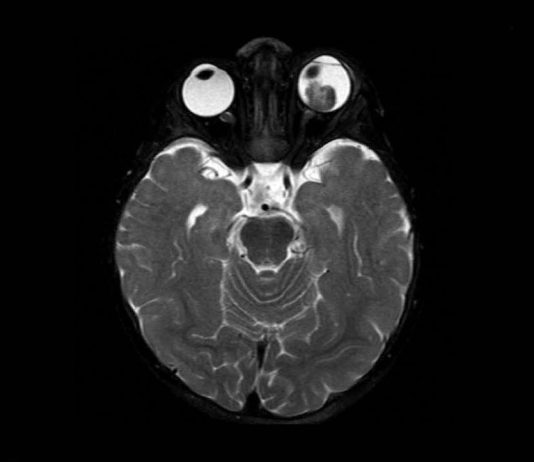

Oncologia oculare pediatrica: approccio clinico, ecografico e diagnosi differenziale in un caso di neoformazione orbitaria